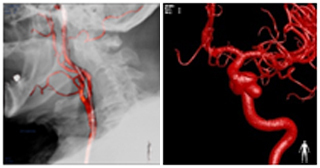

血管造影検査は、動脈または静脈にカテーテルを挿入し、先端を目的部位(脳、心臓、肝臓等)まで進め、血管内に造影剤を注入し血管像や腫瘍像の撮影をする検査です。この検査により、血管の狭窄や閉塞、奇形、出血性病変、腫瘍性病変等を診断・治療することができます。

当院では、4台の血管撮影装置が稼働し、検査や血管内治療を行っています。心臓専用カテーテル室は2室となっており、増え続ける循環器疾患患者様に対しても365日24時間対応しています。

心カテ用の装置には、インターベンションに有用なステントブースト機能や、一度の造影で多方向から撮影できるXperスイング等の機能が搭載され、頭部用にはXperCT・3DRAの機能や、2Dパフュージョン、3D・骨付きロードマップ等充実したワークステーションとなっています。